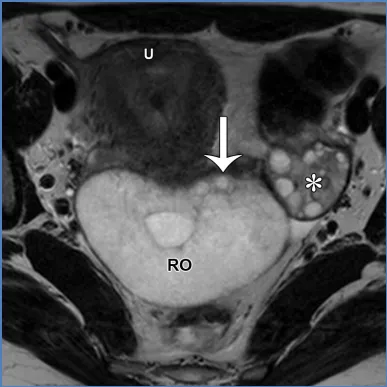

卵巢——卵巢是可活动的腹膜内器官,由卵巢韧带(连接卵巢与子宫角)、卵巢系膜(将卵巢固定于阔韧带)和悬韧带(连接卵巢与盆腔侧壁并包裹性腺血管)支撑(图6)(36)。性腺动脉起源于肾动脉下方的腹主动脉;右侧性腺静脉汇入下腔静脉,左侧性腺静脉汇入左肾静脉。性腺静脉直径大于0.8厘米为异常,尽管性腺静脉直径与静脉反流之间的相关性较差(37)。性腺血管走行于腰大肌前方、输尿管外侧。 卵巢的表现随月经周期阶段和绝经状态而变化。绝经前卵巢为较大的椭圆形结构,在T2加权成像上能清晰显示分区解剖结构,包括T2低信号的皮质、T2等信号的髓质(含疏松排列的基质和血管)、T2高信号的薄壁卵泡,偶尔可见黄体(19,38)。黄体因有黄素化的卵泡膜细胞而呈现T2等信号的厚壁,在退化过程中会变得锯齿状。非出血性黄体中央呈T1低信号、T2高信号,而出血性黄体中央呈T1和T2高信号,有时可见血细胞比容平面。静脉注射对比剂后,卵巢皮质和基质轻度强化,强化程度低于子宫肌层,而黄体壁则表现为早期明显强化(38)。绝经后卵巢比绝经前卵巢小,皮质和髓质呈T2等信号至低信号,偶尔可见小囊肿(38)。表S2以及图7-10详细描述了常见的生理性和其他良性卵巢表现的MRI特征(19,38-42)。图7. 两位不同患者的正常经前卵巢,突出显示了生理学观察结果。(A)示意图显示了带有卵泡的经前卵巢。(B)一位27岁女性患者的轴位T2加权图像显示一个椭圆形卵巢,具有T2低信号皮质(箭头)、T2等信号髓质(白色*)和多个T2高信号卵泡(黑色*)。(C、D)一位30岁女性患者的轴位T2加权(C)和对比增强脂肪抑制T1加权(D)图像显示了黄体(CL),这是经前女性常见的生理学表现。其影像学表现随发育阶段而变化。典型的黄体在T2加权成像上表现为囊性结构,中心呈高信号,壁厚且呈锯齿状,信号强度中等(C中的箭头),在静脉注射造影剂后明显强化(D中的箭头)。图8. 一名34岁闭经女性患者的多囊卵巢综合征与继发性非典型子宫内膜增生。(A)示意图展示了多囊卵巢,这是一种常见的内分泌疾病,影响高达10%的育龄女性。多囊卵巢综合征的诊断依据Rotterdam标准,该标准要求满足以下三项中的至少两项:多囊卵巢、月经稀发或无排卵,以及高雄激素血症。多囊卵巢的定义为:至少一侧卵巢的体积达到10毫升或以上,或者每个卵巢有20个或更多的卵泡(详见表S2)。(B)轴位T2加权图像显示双侧多囊卵巢增大,中央为T2等信号基质(小*),周围有多个T2高信号卵泡。(C)矢状位T2加权图像显示子宫内膜腔内呈不均匀的T2等信号(大*),对应活检证实的非典型子宫内膜增生。在所有增强后序列(包括延迟图像,未显示)中,非典型子宫内膜增生的强化程度低于子宫肌层,这与子宫内膜癌的强化模式相似。图9. 一名27岁女性患者的右侧卵巢扭转,该患者表现为急性盆腔疼痛。轴位T2加权图像显示右侧卵巢(RO)增大且水肿,伴有外周卵泡(箭头所示)。与正常的左侧卵巢(*)相比,右侧卵巢位置异常,位于子宫(U)的中央后方。卵巢扭转的其他表现(未显示)可能包括血管蒂扭转以及强化程度不一,这取决于缺血程度或是否存在梗死。图10. 一位43岁女性患者的输卵管卵巢脓肿,该患者在子宫内膜活检后出现恶心、呕吐和盆腔疼痛症状。轴位T2加权像(A)和对比增强脂肪抑制T1加权像(B)显示左侧附件区有一个多房囊性肿块。该肿块内含有脓性液体,在T2加权像上表现为不同的信号强度(A中的*),并具有增厚的强化壁以及多个强化分隔(B中的箭头)。高b值扩散加权像和ADC图(未显示)显示扩散受限,与脓液的存在相符。经皮引流后获得的细菌培养结果显示大肠杆菌阳性。——输卵管从子宫角延伸至卵巢(39)。近端的壁内部分穿过子宫肌层;远端带有伞端的漏斗部开口于卵巢附近的腹膜腔。输卵管被阔韧带的输卵管系膜包绕(图6)。在MRI上,它们表现为卵巢和子宫之间的T2低信号管状结构。子宫体和宫颈解剖。——子宫由子宫体和宫颈组成,宫颈下段(或子宫颈外口部)突入阴道上部(图2、3)(24、25、43)。在T2加权成像上,绝经前子宫的子宫体(子宫内膜、结合带和外肌层)和宫颈(宫颈管、宫颈内间质和宫颈外间质)均显示出清晰的分区解剖结构。绝经后或接受放射治疗后,这种分区解剖结构会变得不清晰(24、25、43)。子宫内膜腔由均匀的T2高信号子宫内膜衬里,延伸至同样为T2高信号的宫颈管(38)。子宫内膜厚度在子宫矢状面中部沿子宫长轴测量,其数值会随绝经状态和月经周期阶段而变化(表S3)(38、44-49)。对于有绝经后出血的患者,子宫内膜厚度≥5mm为异常;而无症状患者的阈值则不太明确(50)。结合带(子宫内肌层)呈T2低信号,向尾侧延续为T2低信号的宫颈内纤维间质。子宫外肌层呈T2等信号,过渡为宫颈外间质的T2等信号。正常结合带厚度≤8mm,若无微囊肿则可达11mm(45)。 子宫峡部是子宫体与宫颈之间的过渡区,在矢状位T2加权成像上表现为局限性缩窄,在轴位斜向T2加权成像上可见子宫血管进入(图2、3)(24、25)。宫颈内口和外口分别是宫颈管的上下开口。宫颈围绕宫颈管,包括上皮衬里和宫颈间质(43)。宫颈上段由腺状柱状上皮覆盖,宫颈下段(包括子宫颈外口部)由鳞状上皮覆盖。鳞状上皮与柱状上皮的交界处(鳞柱交界)在生育年龄具有动态变化,是大多数宫颈癌前病变和宫颈癌的起源部位。宫旁组织由主韧带和宫骶韧带构成,从宫颈两侧延伸至盆侧壁,包绕子宫血管、神经和输尿管(图2、3)。表S3以及图11-13概述了常见的子宫体和宫颈良性病变的MRI特征(38、44-49)。图11. 一位50岁女性患者的子宫内膜息肉,该患者在乳腺癌切除术后接受他莫昔芬治疗。(A)子宫矢状面示意图显示息肉状子宫内膜病变,伴有因子宫内膜腺体扩张而形成的囊性病灶。(B)冠状斜位T2加权像显示子宫内膜内有一个带蒂病变,具有T2低信号的纤维血管核心(白色箭头)和T2高信号病灶(黑色箭头),这些表现提示为子宫内膜息肉。通常可见明显的强化,与子宫肌层的强化程度相似(未显示)。明确诊断需要宫腔镜下切除,因为子宫内膜息肉、增生和肿瘤可能同时存在,且在影像学特征上可能重叠。偶然可见子宫腺肌症,表现为结合带内存在微囊肿(箭头所示)。图12. 弥漫性和局灶性子宫腺肌病(或子宫腺肌瘤)。(A)子宫矢状面中部的插图显示了弥漫性子宫腺肌病(上图)与局灶性子宫腺肌病或子宫腺肌瘤(下图)的对比。(B、C)两名不同的月经过多患者的矢状位T2加权图像显示,T2低信号的交界区(JZ)弥漫性增厚,伴有散在的T2高信号微囊肿(B中的实线),以及前部交界区伴有微囊肿的局灶性肿块样不对称增厚(C中的虚线)。这些表现是由于子宫肌层内存在异位子宫内膜腺体和间质(微囊肿)以及反应性平滑肌增生(交界区增厚)所致。图13. 纳博特囊肿与隧道簇。插图(A)及两名不同患者的子宫正中矢状面T2加权图像(B、C)显示,浅层宫颈基质内的单房囊肿为典型的纳博特囊肿(A图左图;B图),而向宫颈基质深部延伸的多房囊肿为隧道簇的特征性表现(A图右图;C图)。务必在增强图像上排除强化实性组织的存在(未显示),因为多房性宫颈病变中若出现强化实性组织,应怀疑宫颈胃型腺癌。可能需要进行宫颈锥形活检以明确诊断。子宫在骨盆内的位置会因膀胱充盈程度和盆腔瘢痕情况而有所不同。倾位指的是宫颈与阴道之间的角度:前倾位是向前倾斜,后倾位是向后倾斜(图14)(38)。屈曲描述的是子宫体与宫颈之间的角度:前屈是向前弯曲,后屈是向后弯曲(38)。图14. 插图(A)和磁共振图像(B、C)显示了女性骨盆内子宫的各种位置。子宫倾(Version)指的是宫颈与阴道之间的角度:A中的上组插图将该角度显示为黄线相对于红线的倾斜度。前倾(Anteversion)指向前倾斜,后倾(Retroversion)指向后倾斜。子宫屈(Flexion)描述的是子宫体与宫颈之间的角度:A中的下组插图将该角度显示为蓝线相对于黄线的倾斜度。前屈(Anteflexion)指向前弯曲,后屈(Retroflexion)指向后弯曲。两名患者的矢状位T2加权图像(B、C)中,B显示的是前倾前屈位子宫,C显示的是后倾后屈位子宫。阴道是一个纤维肌性结构,通过膀胱阴道隔与膀胱相隔,通过直肠阴道隔与直肠相隔(图4)(51)。在轴位T2加权成像上,绝经前阴道通常呈H形或W形塌陷,具有高信号的黏膜皱襞和低信号的壁。绝经后,皱襞消失,阴道壁厚度变薄。阴道上部有由突出的宫颈形成的穹窿,阴道下部通过阴道口开口于外阴前庭。表S4和图15详细描述了常见良性阴道病变的MRI特征(51-53)。图15. 四个不同患者的矢状面示意图(A)和轴位T2加权图像(B–E)显示了阴道囊肿、斯基恩氏腺囊肿以及尿道憩室。巴氏腺囊肿:位于耻骨联合处或其下方阴道后外侧壁的单房囊肿(A中的灰色椭圆形,B中的T2高信号囊性病变)。加特纳管囊肿:位于耻骨联合处或其上方阴道前外侧壁的单房囊肿(A中的蓝色椭圆形,C中的T2高信号囊性病变)。斯基恩氏腺囊肿:位于耻骨联合下方、阴道前方、尿道下段外侧的单侧或双侧小单房囊肿(A中的浅黄色椭圆形,D中的T2高信号囊性病变)。尿道憩室:在耻骨联合附近,尿道中远端后外侧出现的圆形、椭圆形或U形T2高信号液性囊袋状突起(A中的尿道囊袋状突起)。在罕见情况下,尿道憩室可能完全环绕尿道(E中的T2高信号环形囊性病变)。外阴由女性外生殖器组成(图16)(53)。阴阜位于耻骨联合前方,由脂肪组织构成。大阴唇是位于阴阜下方并与其相连的厚皮肤皱襞。小阴唇是大阴唇之间较薄的皱襞,向前会合于阴蒂头。小阴唇之间的前庭包含尿道外口(尿道口)和阴道口(阴道开口)。图16. 示意图(A)和轴位T2加权图像(B)显示了外阴区域或女性外生殖器。阴阜位于耻骨联合前方,由脂肪组织构成。大阴唇是位于阴阜下方且与其相连的厚皮肤皱襞。小阴唇是大阴唇之间较薄的皱襞,向前汇聚于阴蒂头。小阴唇之间的前庭前部有尿道外口(尿道口),后部有阴道口(阴道开口)。参考文献:https://doi.org/10.1148/rg.250029